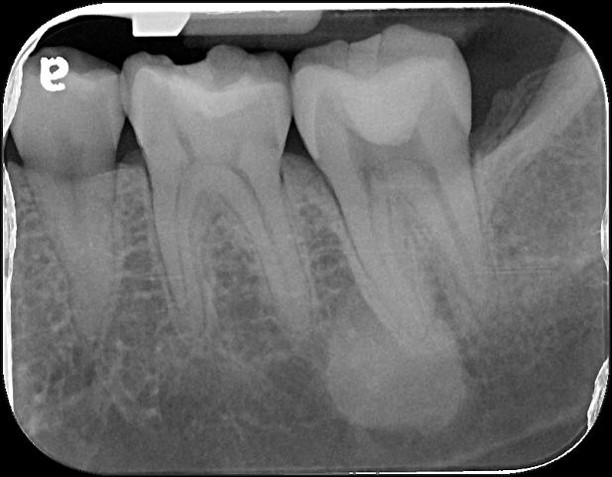

顯微根管治療